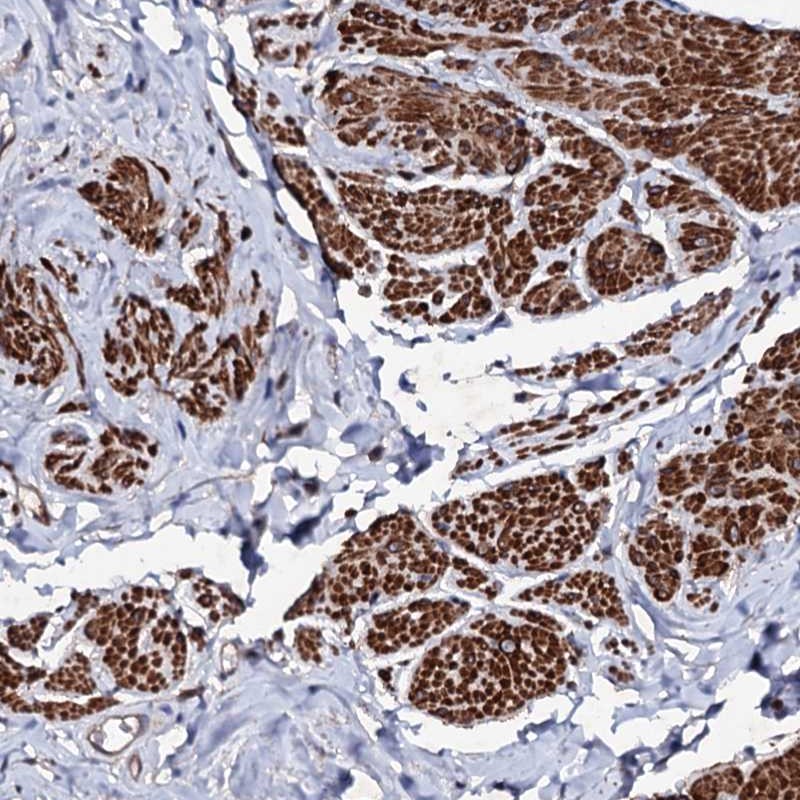

Immunohistochemical staining of human smooth muscle shows strong cytoplasmic positivity.